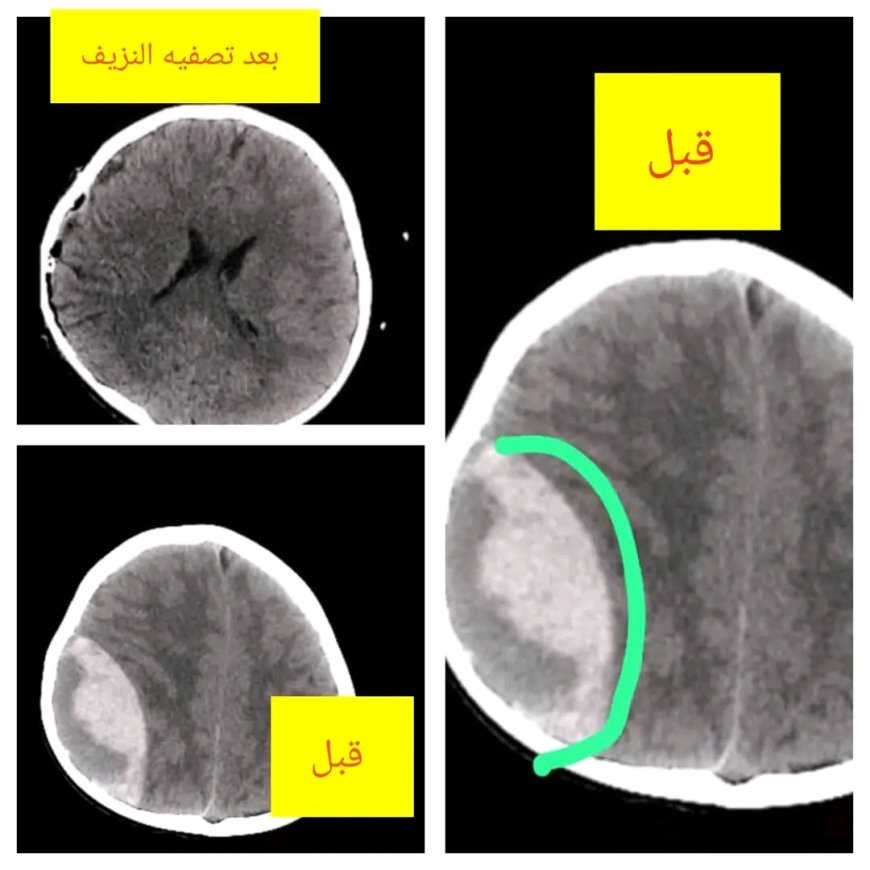

وكشفت نتائج الأشعة المقطعية (CT Scan) عن وجود نزيف دموي كبير فوق الجافية في الجهة اليسرى من الدماغ (Epidural Hematoma)، وهي من الحالات الخطيرة التي قد تؤدي إلى الوفاة في حال عدم التدخل الجراحي السريع.

وأمام خطورة الوضع، اتخذ استشاري جراحة المخ والأعصاب الدكتور عمر السروري القرار الفوري بإجراء عملية جراحية طارئة ودقيقة، تم خلالها فتح المنطقة المتضررة وتفريغ النزيف والسيطرة عليه وتنظيفها وفق المعايير الطبية المتبعة، بمشاركة فريق التخدير بقيادة الدكتور إبراهيم الأشول وطاقمه الفني، الذين كان لدورهم أثر بالغ في إنجاح العملية وإدارة الحالة طوال فترة الجراحة.

وفي اليوم الثالث من المتابعة، تقرر نقل الطفل إلى قسم الرقود وهو في حالة صحية جيدة وبكامل وعيه، مع السماح له بالبدء بالتغذية، ليعود لاحقاً إلى أسرته دون أي مضاعفات تُذكر.